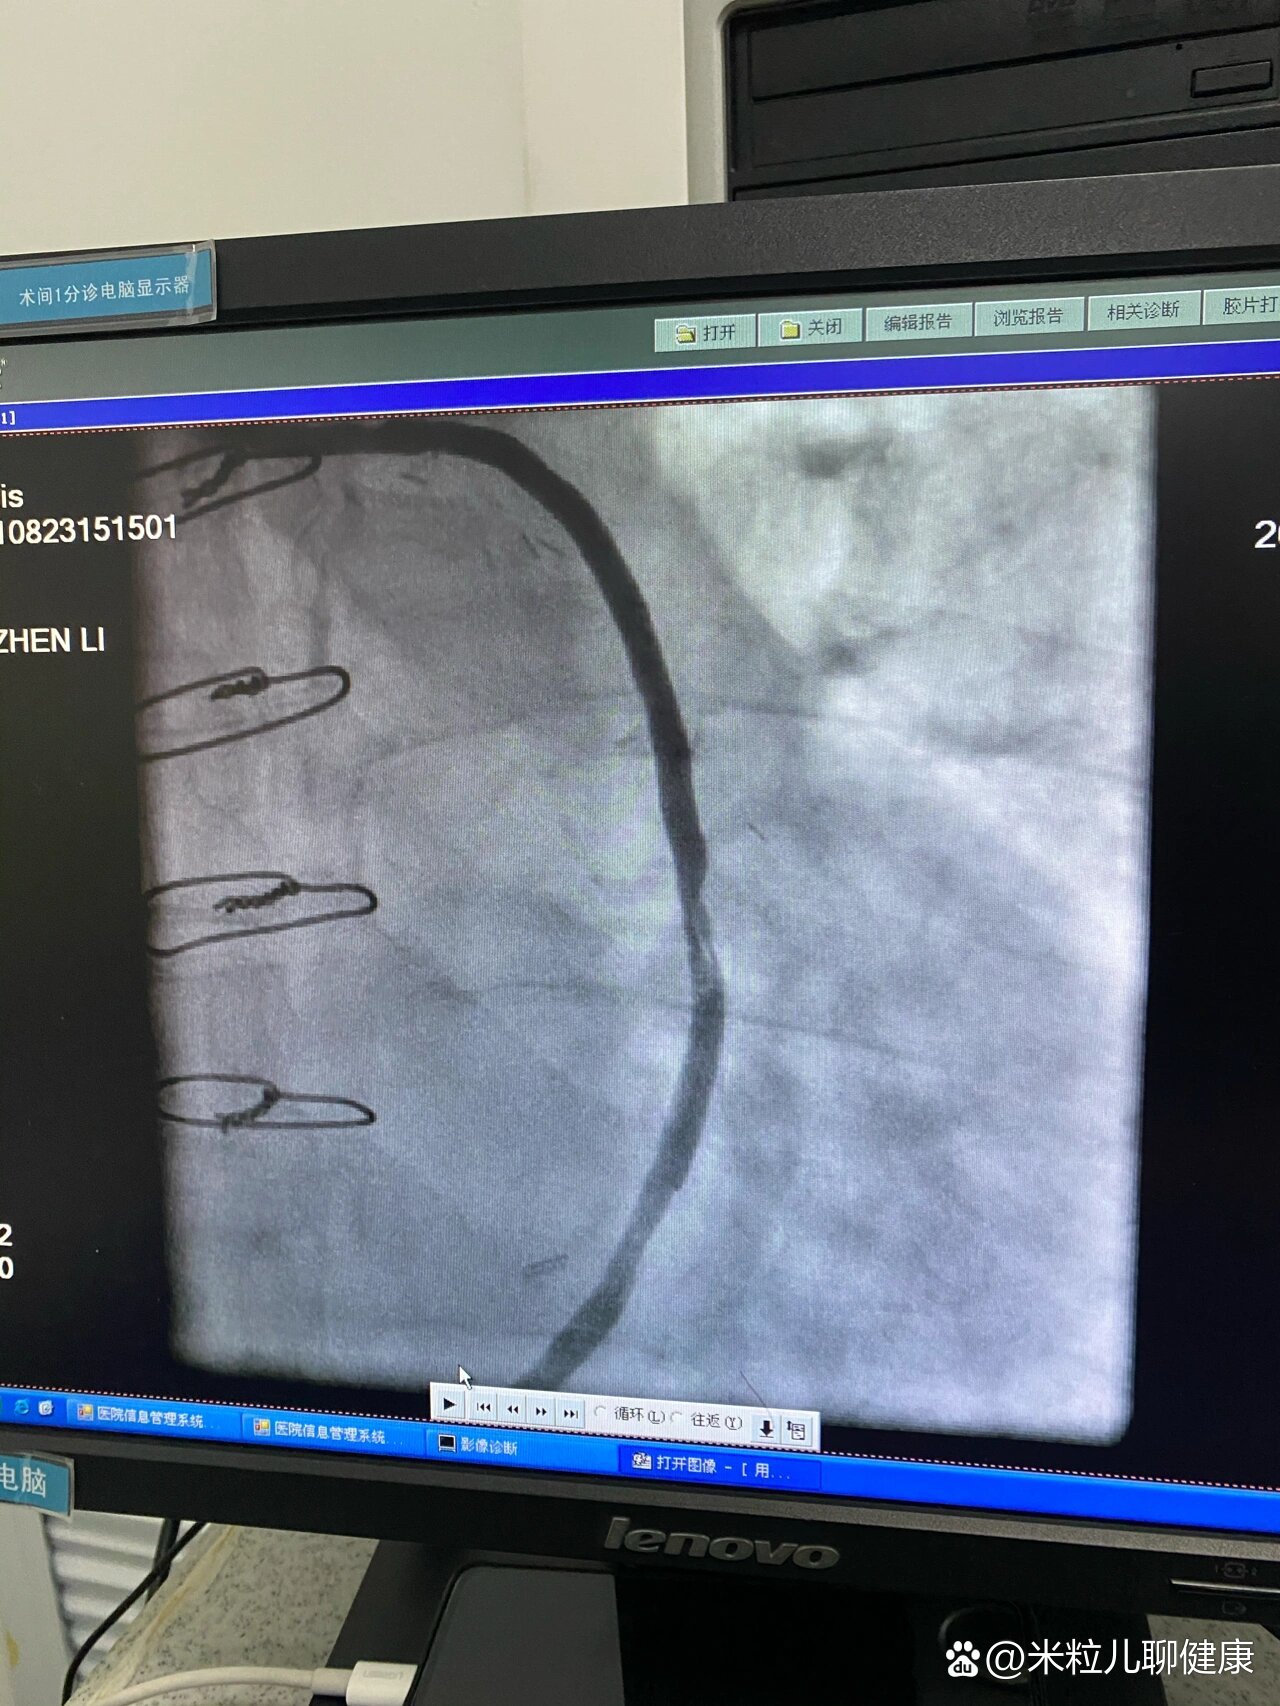

冠脉造影术前术后图片

我又做冠脉造影( coronary angiography )了 - 知乎